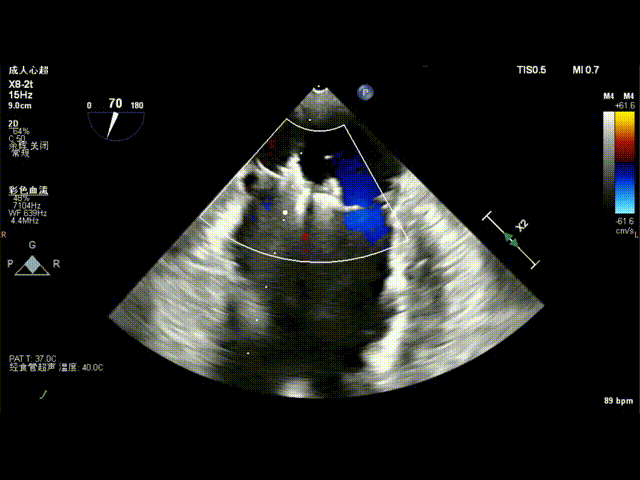

第一枚夹合器夹合3D血流

调整第二枚NeoNova ® C6夹合器orientation,将其送至1区内侧残余脱垂处,定位后 Clasp 捕获瓣叶,注意瓣叶张力,缓慢收紧 Paddle ,食道超声3D界面评估组织桥稳定,可见脱垂基本消失,未见明显反流来源。

第二枚夹合器夹合后3D血流